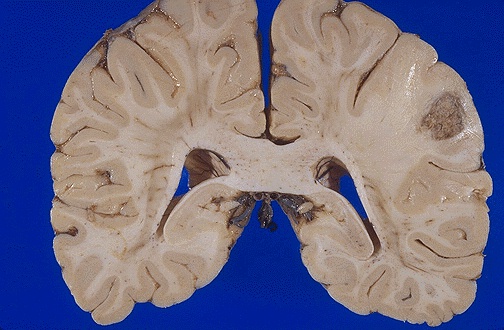

![]() | Seen here is a metastasis from a lung carcinoma. Metastases most often appear at the border of the grey and white matter in the distribution of the middle cerebral artery, as in this case, because that is where the blood flow (vascular distribution) is most likely to take metastases. [Image contributed by Jeannette J. Townsend, MD, University of Utah] |